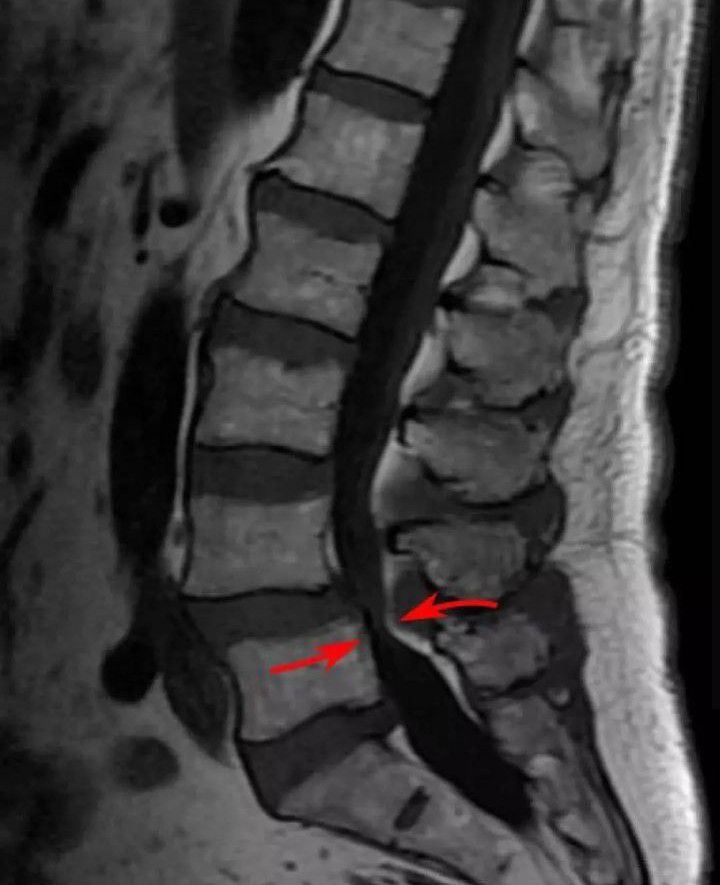

Magnetic resonance imaging (MRI) of a lumbar spinal stenosis L4-L5. L4-L5 antherolisthesis of grade I. Hypertrophy of interspinous ligaments in relation to Baastrup's disease